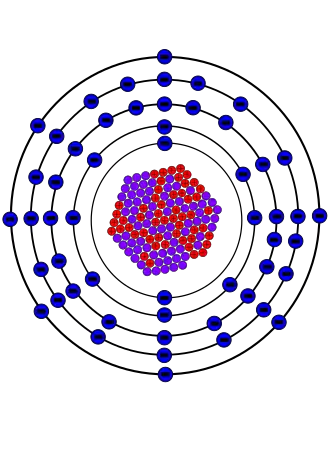

Иод-125

| Название, символ | Иод-125, 125I |

| Нейтронов | 72 |

Иод-125 (йод-125, 125I) — искусственный радиоактивный изотоп иода. Нашёл применение в медицине для лечения онкологических заболеваний.